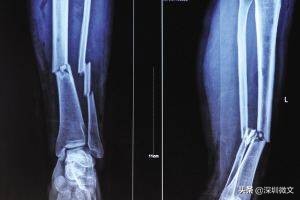

【X光:将人体骨骼投射到同一个平面上进行成像】

举两个例子说明一下医生怎么通过“黑白色差”判断病情:

一、比方说某患者小腿出现明显骨折,那他骨折处对X光的吸收量就与周边骨干呈现出明显对比,骨折处就会出现一条明显的黑色裂痕。再者,医生也会通过白色“画成”的骨干是否有异常变形做判断。

二、部分患者并非因为骨折去拍片,而是因为骨头里进了异物。要想通过手术取出来,首先得准确判断异物在骨干精确到毫米的位置。医生怎么判断呢?异物在骨头内对X光的吸收量不同,那个点就会与周边骨干呈现出明显色差,一般是白色的骨干当中出现明显的黑点。通过这一异常医生就可以锁定异物位置。

X光一般是初筛,对体内异物的直观诊断。对于有移位骨折、有骨质改变的骨病、关节部位骨性病变、不透光异物存留、心肺器质性疾病、消化系统梗阻等疾病有很好的诊断价值。X光的优点是对于骨干病变的诊断,但对于体内的软组织检查没有太多效果。